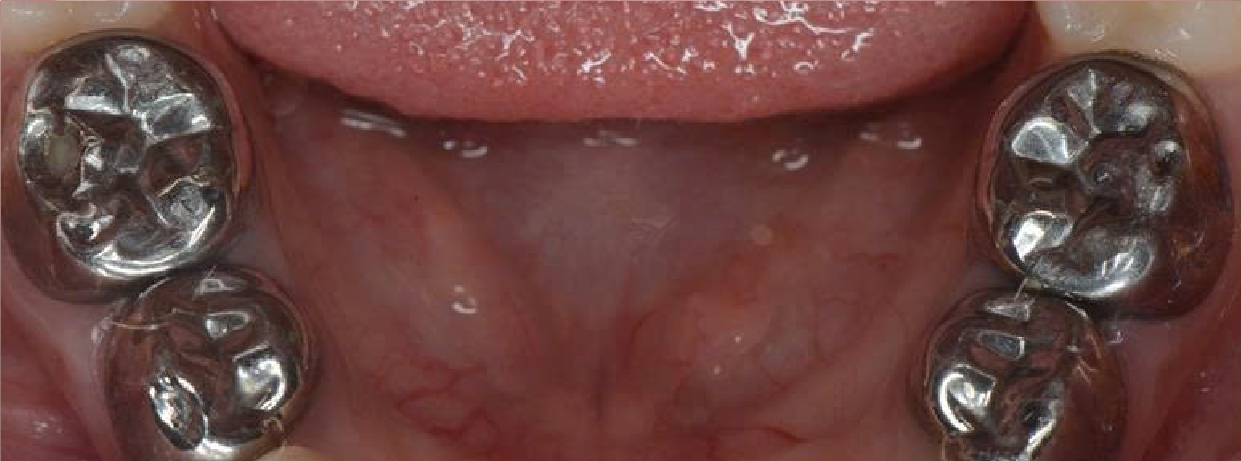

Hình Ảnh Trước & Sau Điều Trị

Minh chứng rõ ràng cho chất lượng và hiệu quả tại Nha khoa Như Ngọc – nơi mỗi khách hàng đều tìm lại được nụ cười tự tin sau quá trình điều trị và thẩm mỹ răng